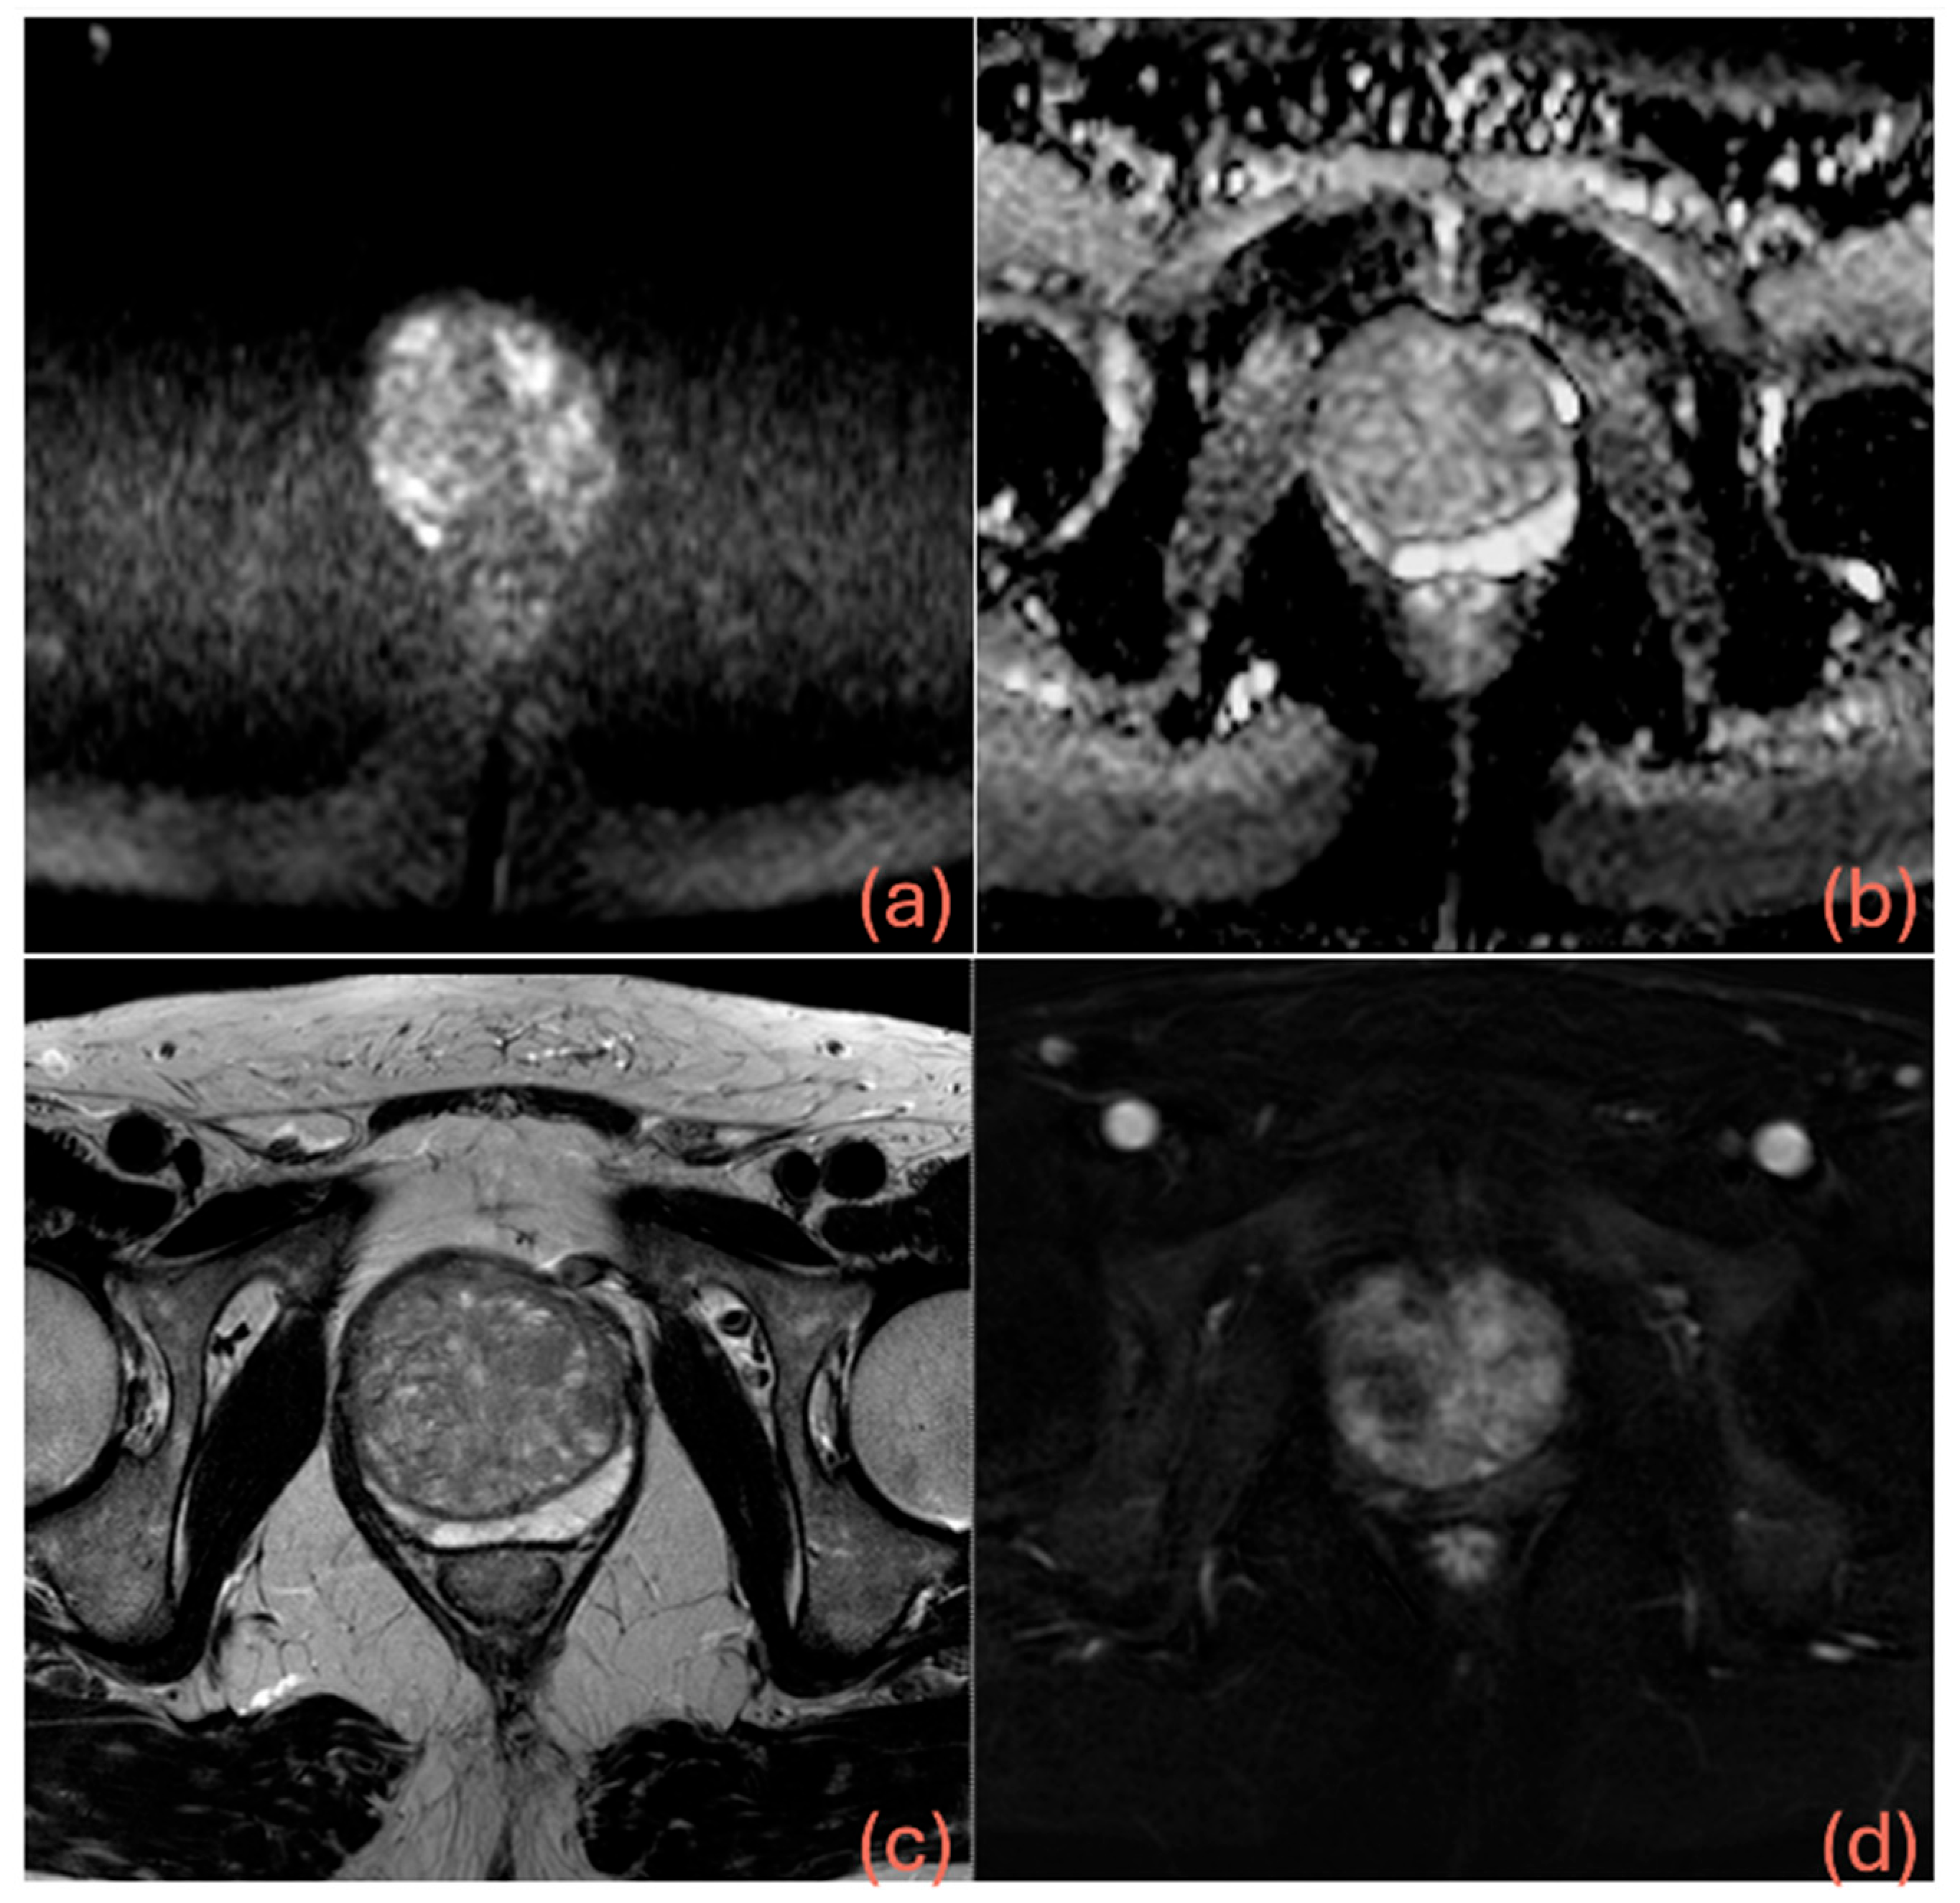

Table 2 shows the results of logistic regression, while Table 3 presents a summary of the diagnostic performance metrics for assessing csPCa, along with the thresholds derived from ROC analysis and details on the grading group od missed cancers. Figure 3 displays the AUCs for the three models, showing that both M2 (p = 0.0188) and M3 (p < 0.0001) achieved significantly higher AUCs than M1. Additionally, the AUC for M3 was significantly higher than that of M2 (p = 0.0003). Miss rate for csPca was 12.6% for M1 (24/190), 8.4% for M2 (16/190) and 13.2% for M3 (25/190). Figure 4 shows the confusion matrices for M1, M2 and M3, while Figure 5 shows an MRI example case.

Figure 5. A 60-year-old man with PSA of 20 ng/mL, PSAD of 0.13 ng/mL/mL, negative digital rectal examination (DRE), no prior biopsy, and on tamsulosin therapy. MRI showed a prostate volume of 150 mL and revealed a 5 mm PIRADS 4 focal lesion in the right posteromedial peripheral zone at the apex—demonstrating hyperintensity on high b-value DWI (a), hypointensity on the ADC map (b) and T2-weighted images (c), and focal early enhancement on DCE (d). The lesion was classified as negative by model 1, positive by model 2, and negative by model 3. The latter classification could have potentially avoided an unnecessary biopsy, which was ultimately negative for prostate cancer on both targeted and perilesional sampling.